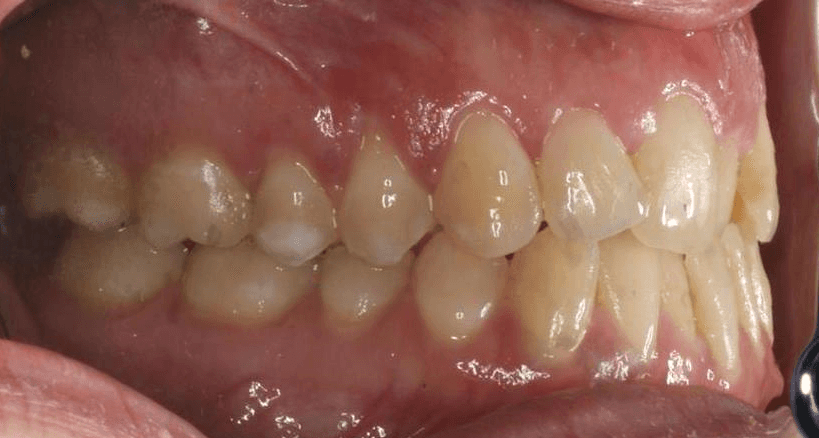

Diganosis: Moderate crowding in both arches, constricted arch forms with anterior and posterior single tooth crossbites, poor smile display

Adjuncts: Occlusal turbos, elastics, attachments, IPR

Initial treatment

INTRAORAL